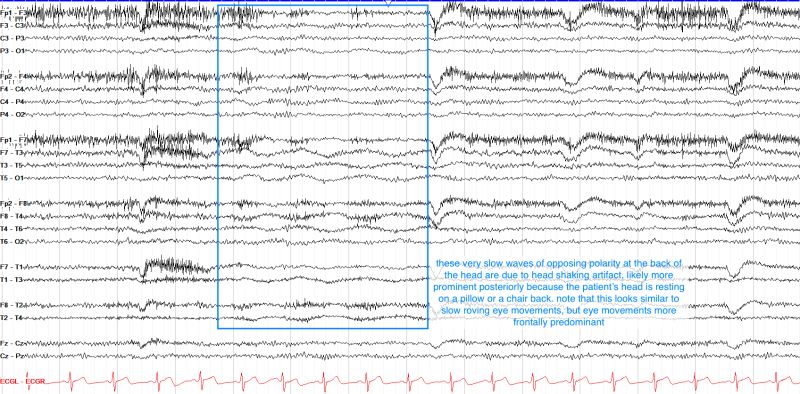

- BME | EEG Analysis - Hilbert Transform | Aursus